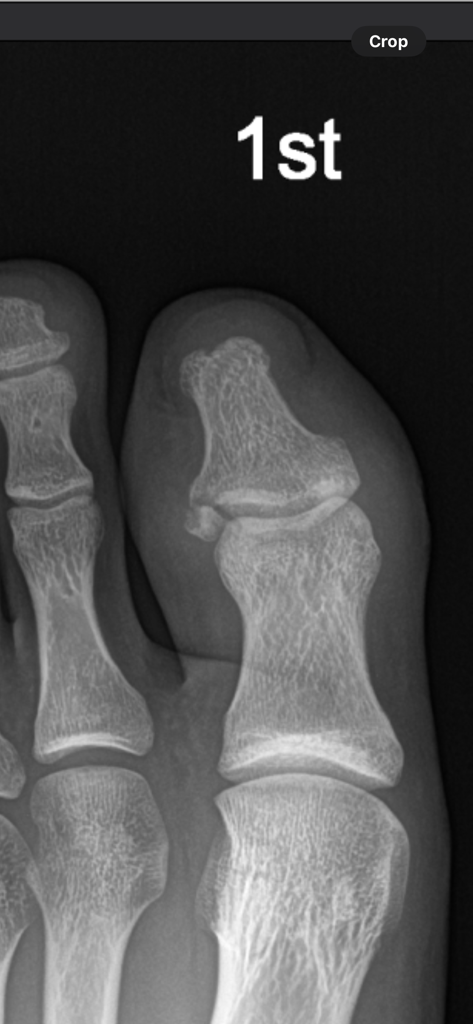

이렇게 원위지골의 전위가 발생하여 불유합 가능성이 높다고 진단을 받았습니다. 저렇게 뼈가 조각나서 전위가 발생했네요.

1) 혹시 수술적 치료를 하면 핀을 박는 수술을 하나요? 아니면 저 조각난 뼈를 제거하는 수술을 하나요?

2) 저정도 크기의 뼈조각이면 핀으로 고정할 수 있는 정도인가요?

우선 전위된 골의 크기가 매우 작아 핀으로 고정하기에 상당히 어려우며 이미 2주가 지난 상태이기 때문에 핀으로 고정을 한다 하더라도 완전히 밀착이 되지 않을 수 있어 골유합에 도움이 되지 않을수도 있습니다.

그렇기 때문에 의사에 따라 판단이 다를 수도 있겠지만 조금더 기다려 보신 후 추후 통증을 유발하는 상황이라면 제거술을 병행하시는 선택을 할 것 같습니다.